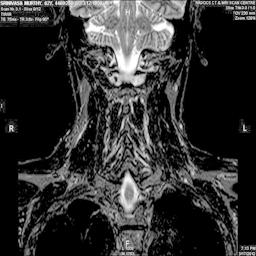

The developed algorithm presented in the previous section was coded using Matlab Version 8.0. The experiment was conducted by considering poor quality spinal cord images of having various lesions. The first column of Fig. 4 shows the axial view of neck spinal cord images of size pixels, respectively. The second column of Fig. 4 presents the same images enhanced using histogram equalization. As is evident from the results presented, the histogram equalization method performs global image enhancement operation which improves the contrast of an image but at the cost loss in image details. The third column of Fig. 4 shows the MSR based spinal cord image enhancement. It can be seen that from the result presented, MSR scheme improves the details that are not clearly visible in histogram equalization technique. In general, image enhancement achieved by MSR method is better compared to histogram equalization. However, the MSR method voilates gray world assumption. Therefore, the image enhanced by this scheme appears to be grayish. Although, numerous work have been reported for solving the problem due to gray world voilation, no work seems to developed for complete elimination.

The fourth column of Fig. 4 shows the image enhanced using Chao et al. []. It can be seen from the results presented that the reconstructed images of Chao’s method have black spots. The appearance of these dark patches degrades the visual quality of the enhanced image. The image enhanced using proposed multirate multiscale retinex image enhancement method presented in the fifth column of Fig. 4, overcomes the drawback of the Chao’s method. As we can see from the simulation results, image enhancement achieved by the proposed method has improved details with significant contrast enhancement. The enhanced images from the proposed method provides information to physicians, radiologists and researchers for various types of pathology detection.